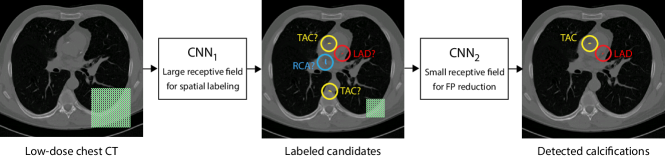

The proposed method for automatic detection of CAC, TAC and calcifications of the aortic and mitral valves consists of two steps. Each step uses a CNN to classify voxels in the image. The first CNN (CNN1) has a large receptive field to be able to detect calcium based on the anatomical context and to label calcium voxels according to their anatomical location. The second CNN (CNN2) has a smaller receptive field and discards false positives based on local image information. Only voxels that CNN1 considers calcium are classified by CNN2 as either true-positive or false-positive (Figure 2).

We proposed a method for automatic detection of CAC subdivided into LAD, LCX and RCA calcifications, TAC and cardiac valve calcifications in low-dose chest CT. The method is the first that detects these calcifications concurrently. The approach is based on two consecutive CNNs: The first CNN uses stacked dilated convolutions to facilitate a large receptive field, which enables identification and spatial labeling of high density voxels. The second CNN discards false positive detections of the first CNN.